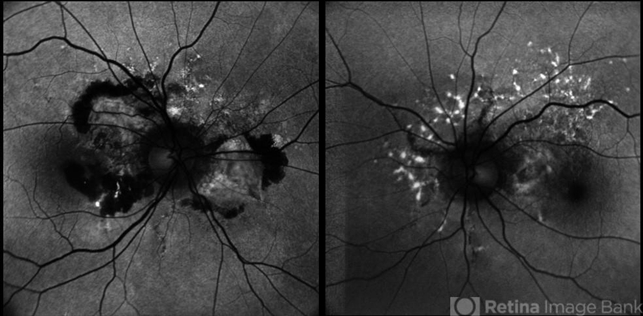

- fundus autofluorescence (FAF), choroidal neovascular membrane (CNVM), Angioid Streaks

- A 45 year old male came with chief complaint of blurring vision in right eyes since past 4 days. His vision is 6/12 in right eye and 6/9 in left eye. His vision was 14 mmHg in right eye and 16 mmHg in left eye. He was diagnosed with Angioid Streaks in both eyes about a year ago, then he developed choroidal neovascularization in his left eye 8 months ago, for which he received AntiVEGF injections x 3. Left eye is a stable eye now. Patient presented with right eye choroidal neovascularization in a case of Angioid Streaks on recent follow up. We have advised him right eye AntiVEGF injections x 3. In this image we can see fundus hypoautofluorescence in right eye due to hemorrhages and angioid streaks and in left eye fundus hypoautofluorescence is noted due to angioid streaks.